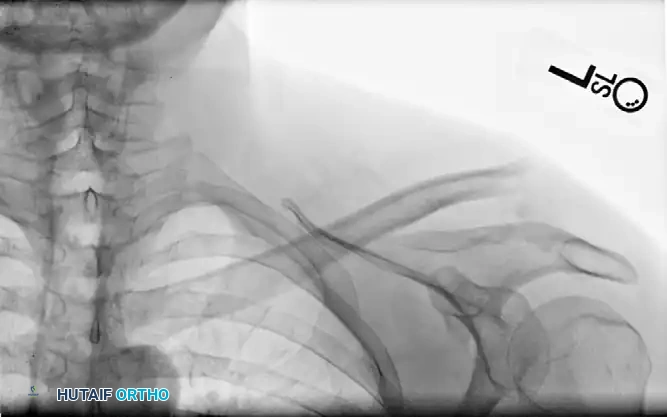

Postoperative Fixation: The fracture is anatomically reduced and stabilized using a clavicular hook plate. The hook is engaged beneath the acromion, neutralizing superior translation.

Image